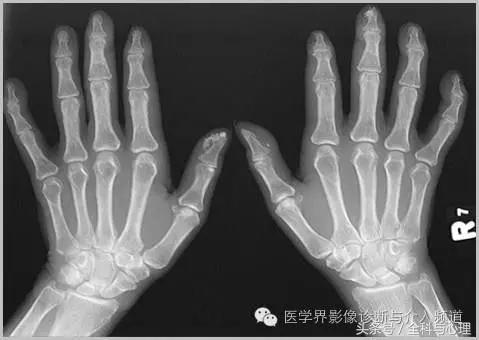

2、 与硬皮病相关的手部局限性钙质沉积

手部皮肤或皮下组织,多发的,边界清晰的,点状、片状的钙化灶,与硬皮病相关。

软组织钙化与骨化,软组织钙化和骨质增生 硬皮病

软组织钙化与骨化,软组织钙化和骨质增生

硬皮病